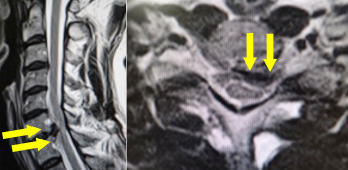

左から脊髄髄外腫瘍、脊髄髄内腫瘍、馬尾腫瘍のMRI画像です。